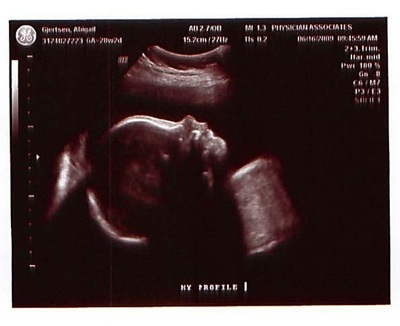

Tuesday was a 28-week ultrasound for #3 (we’ll reveal the puzzle solution with his name soon!). Thankfully it went much better than Dora’s did. He was in a good position for us to measure his growth as well as see his cute little face!

After two pregnancies that defied all the odds, it’s a relief to be “just” average. At the appointment we discovered that #3 is in the 56th percentile for growth, already weighing approximately 2 lbs. 12 oz.! That means he’s right in the middle of typical—a good thing, since James was in the 1st percentile and weighed 2 lbs. 14 oz. when he was born at 35 weeks.

And what do you think—does he look like James or not? The first two pics are #3, and the last two are James a week younger:

Yes, they sure do look like brothers.